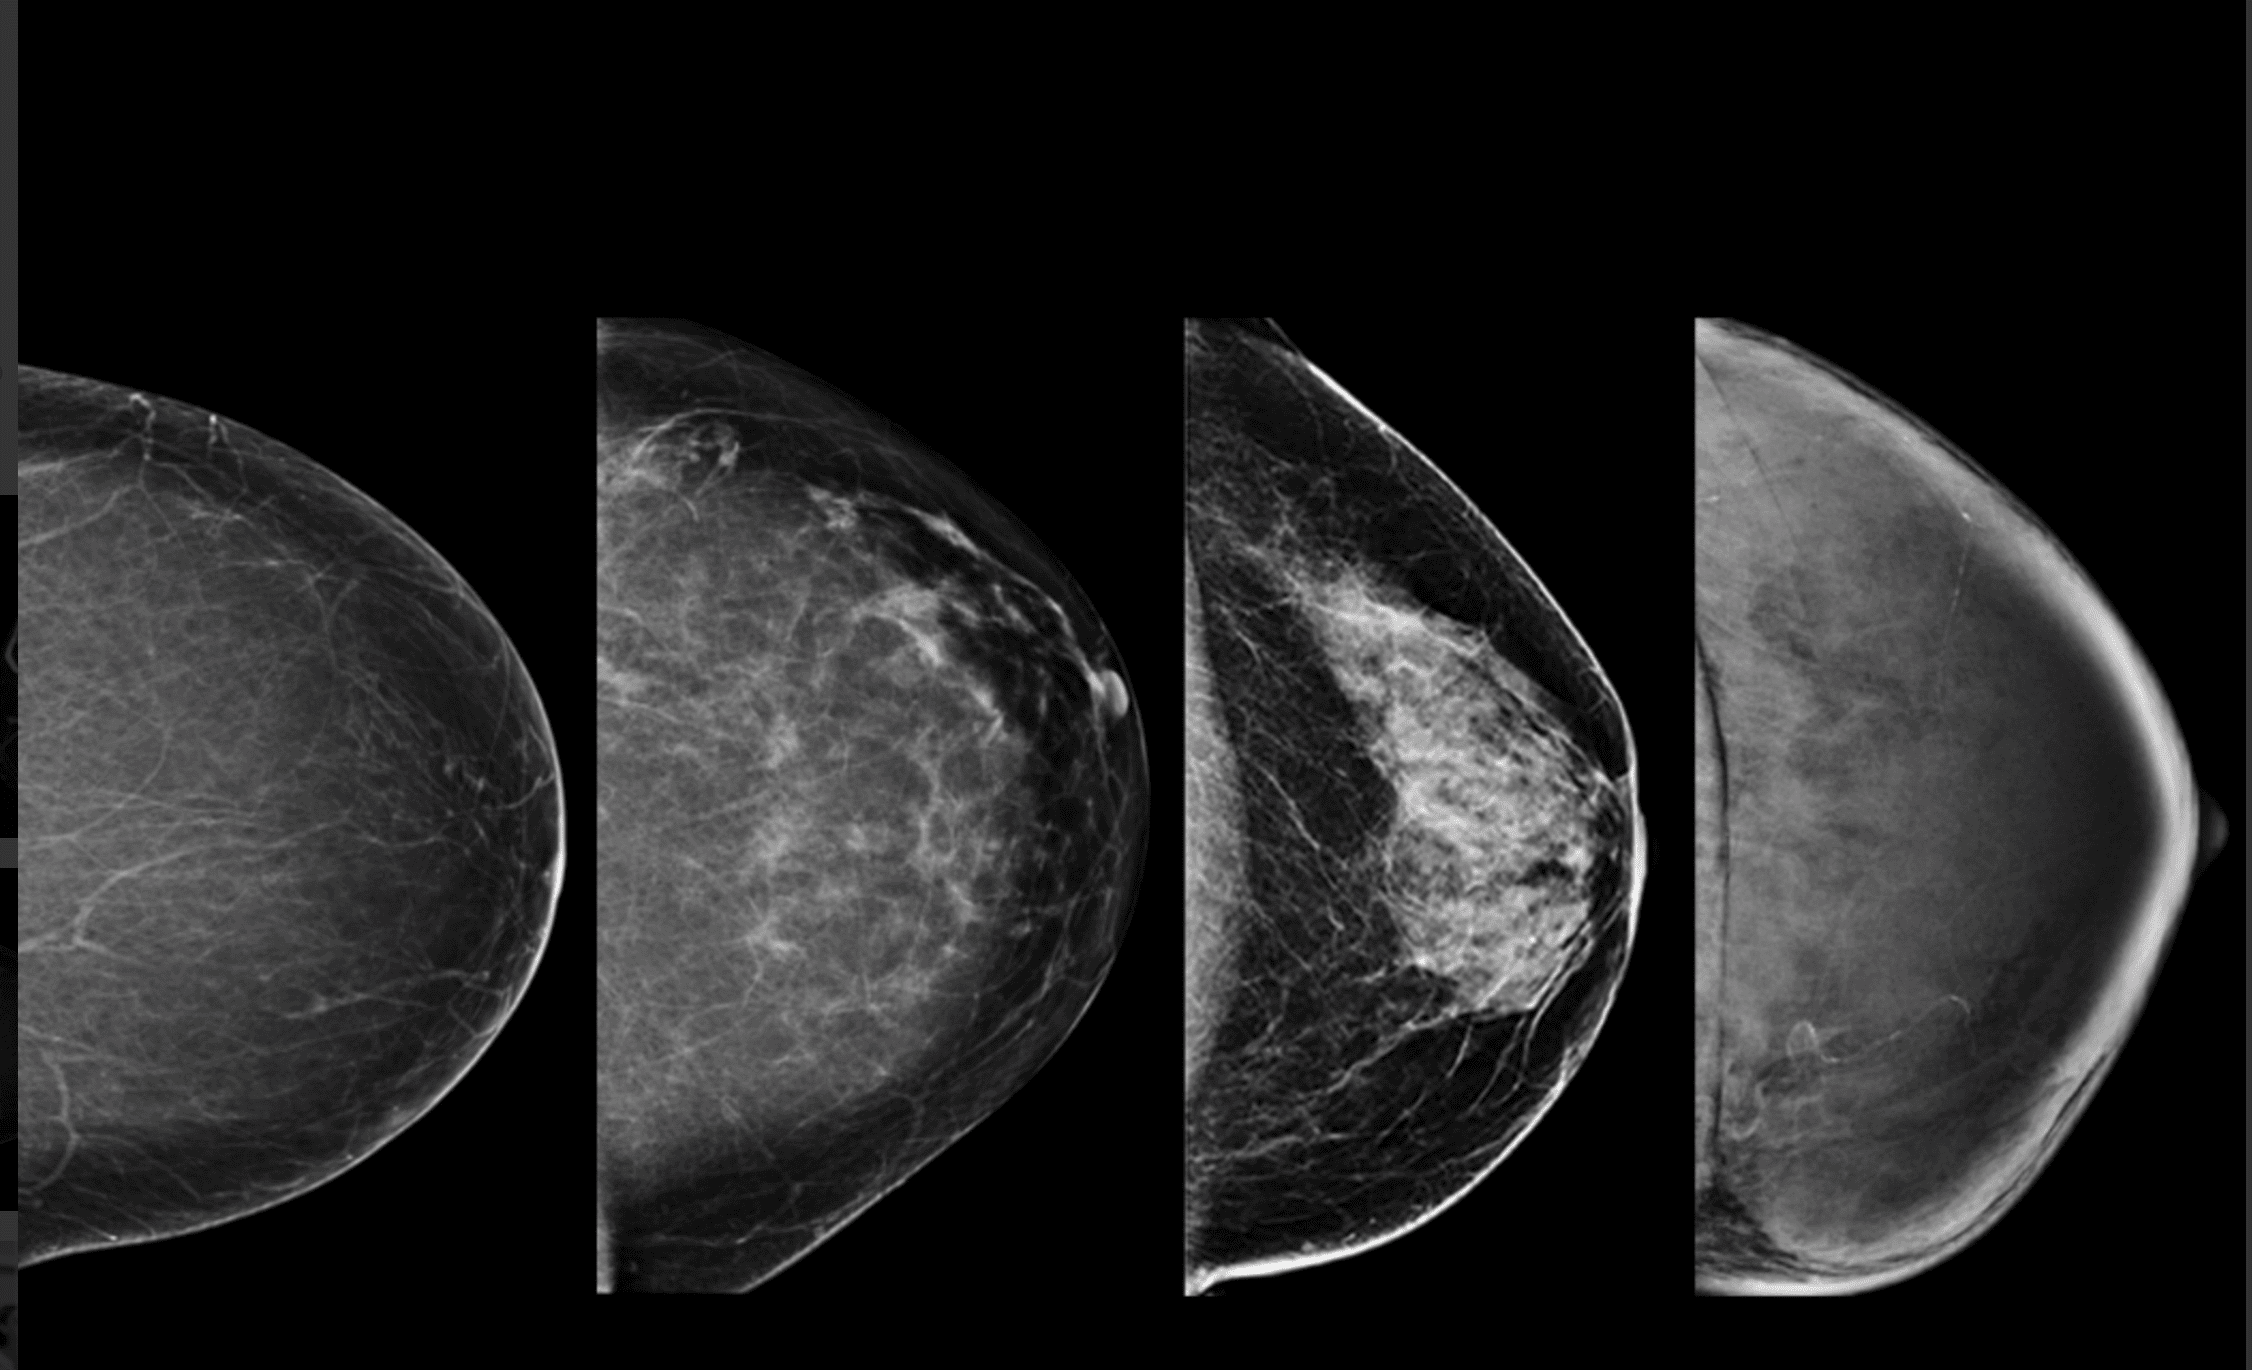

– Tessék derékig levetkőzni. Lépjen közelebb. Hajoljon kicsit le. Ne dugja a képbe a karját. Az állát fordítsa el. Most eressze le a vállát. A testével forduljon a fal felé. Dőljön előre kicsit. Fogja meg a másik kezével a rudat. Ne mozogjon. Nem jó, homályos lett, még egyszer. Ja, ezt itt el lehet forgatni. Ez egy új gép, most tanuljuk mi is. Most a másikat. Azt hittem, ez majd jobban megy. Ne rogyassza be a térdét. Húzza ki magát. Most dőljön a gép felé, és forduljon, ahogy az előbb, csak fordítva. És kicsit hajlítsa be a térdét. Öltözzön fel és üljön le kint.

– Vetkőzzön le a függöny mögött derékig. Mindent hagyjon ott. Adok lábzacskót. Adja ide a régi felvételeit. Nézzük. Ez a bal, ez a jobb. Feküdjön le. Nem, fordítva. Ez mikori? Mondtam, hogy feküdjön le. A régi CD-jét nem tudjuk beolvasni, új a gép. Ma dolgozunk vele először. Aha, ide vetíti a balt, ide a jobbat. Nem, először a bal két felvételét, aztán a jobbét együtt, összerakja. Feküdjön már le, mit nézeget. Látod, ez a kettő jön fel először. Na nézzük. Feküdjön hanyatt. Forduljon felém. Úgy, nagyon jó. Készen vagyunk. Ezt kiveszem maga alól, ezzel megtörölközhet.

kép | healthimaging.com